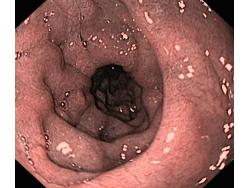

Celiakia